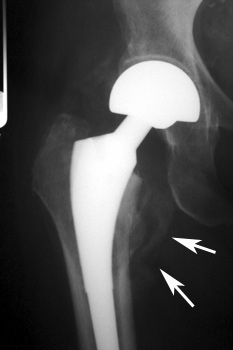

HETEROTOPIC BONE FORMATION—Early heterotopic ossification (arrows) occurring 6 weeks after surgery